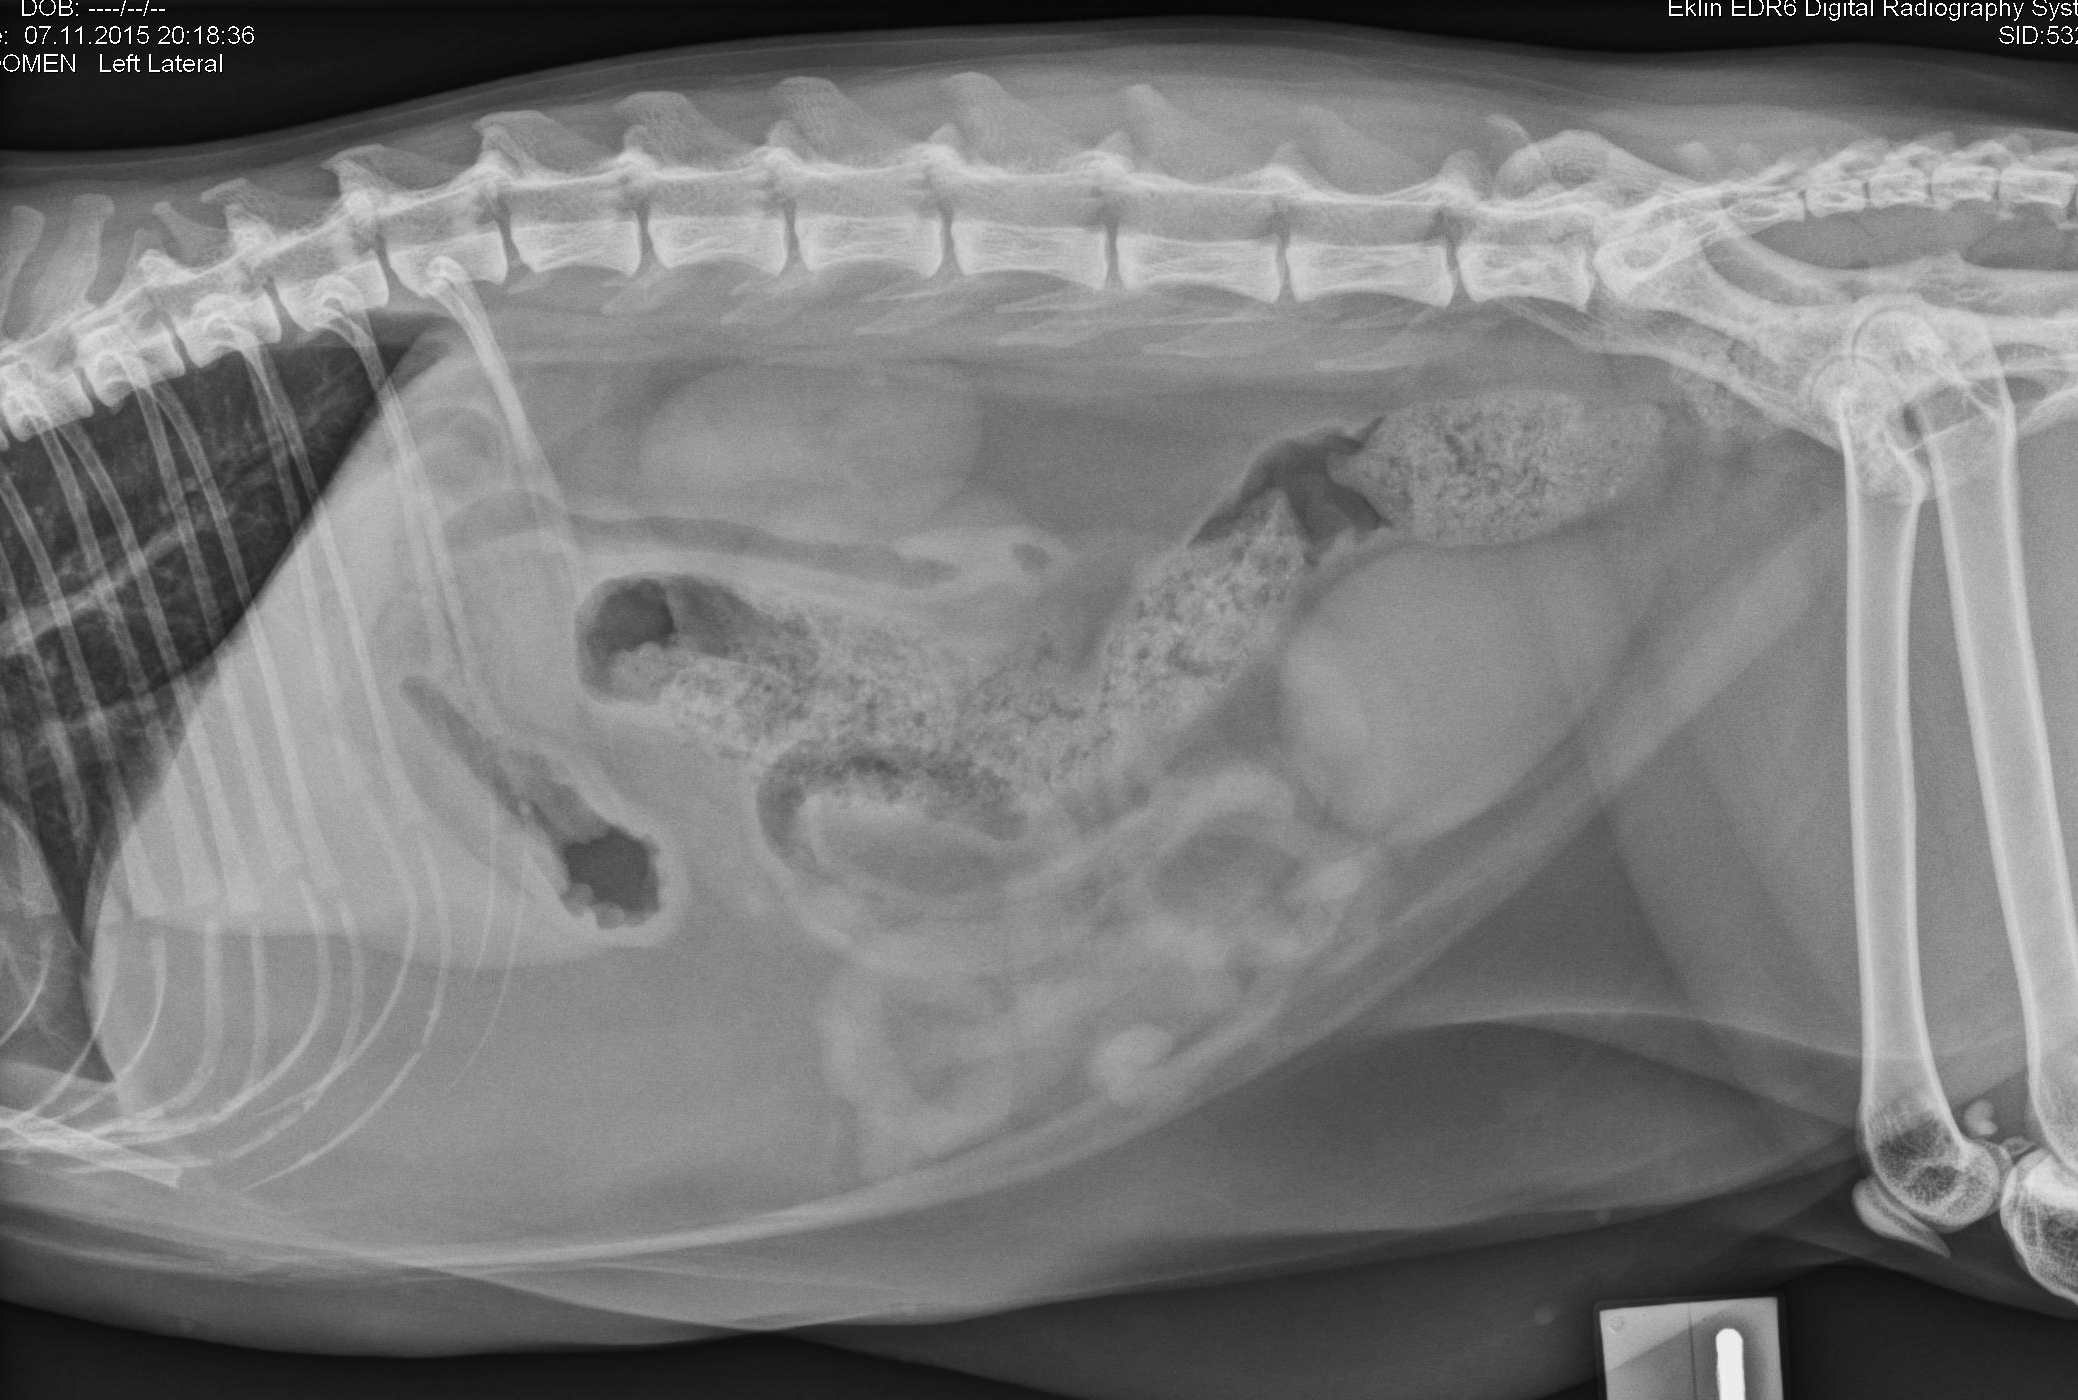

Latérale gauche